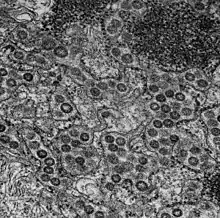

Cellule MRC-5